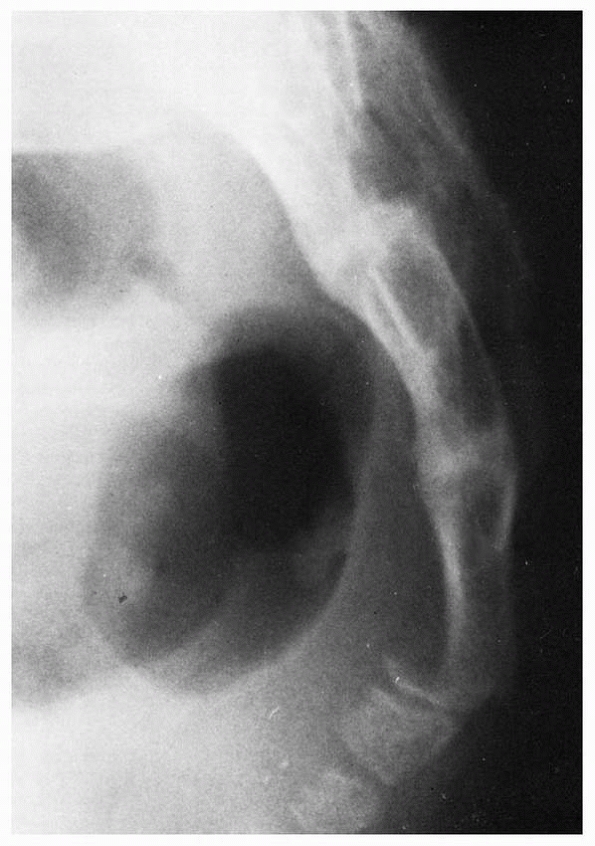

the hips flexed maximally may reveal a fracture (Fig. 20-23).

FIGURE 20-23 Lateral radiograph with the hips maximally flexed reveals displaced coccygeal fracture in a 14-year-old boy.